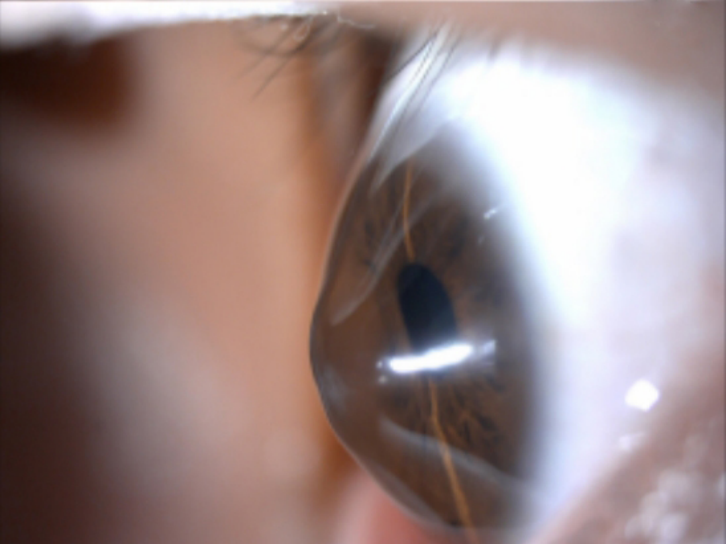

简单来说,正常角膜是均匀的“球面”,而圆锥角膜是一种以角膜中央或旁中央向前突出呈圆锥形为特征的先天性角膜发育异常,简单来说,就是角膜从原本的“球面”变成了“圆锥面”。这种病变会导致角膜逐渐变薄、不规则散光增加,进而严重影响视力。

它并非普通的屈光不正,而是一种进行性角膜病变。初期仅表现为散光、近视加深,很容易被误诊为普通屈光不正;随着病情发展,角膜突出越来越明显,视力会持续下降,即便戴框架眼镜也难以矫正。